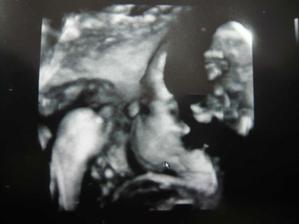

Nasa mala

patrime k stastnym nastavajucim rodicom, ktori to skusili parkrat v jednom mesiac i/jul/ a tak necakane dosli k malej babulke. uz od 11tt vieme ze budeme mat dievcatko vdaka testom ktore sa robia z krvi a velmi sa tesime. boli sme nedockavi cakat az na ultrazvuk a ked bola takato moznost preco nie... :D

tak teraz len dufame ze budeme pekne rast a budeme zdrave